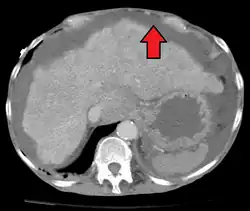

| Diagnostic method | Physical exam, ultrasound, CT scan[3] |

In the developed world, the most common cause is liver cirrhosis, whose underlying mechanism involves high blood pressure in the portal system and dysfunction of blood vessels. Other causes include cancer, heart failure, tuberculosis, pancreatitis, and blockage of the hepatic vein.[4] Diagnosis is typically based on an examination together with ultrasound or a CT scan. Testing the fluid can help in determining the underlying cause.[3]

Ultrasound investigation is often done before attempts to remove fluid from the abdomen. This may reveal the size and shape of the abdominal organs, and Doppler studies may show the direction of flow in the portal vein, as well as detecting Budd–Chiari syndrome (thrombosis of the hepatic vein) and portal vein thrombosis. The sonographer also can estimate the amount of ascitic fluid, and difficult-to-drain ascites may be drained under ultrasound guidance. An abdominal CT scan is more accurate than a sonogram to reveal abdominal organ structure and morphology.[13]